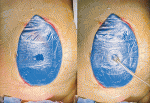

Towel clip closure,Silo closure(Bogota bag),Vacuum packing closure(VPC)等が行われてきた.VPCは浸出液のコントロールが良好で,腹壁の退縮を軽減でき,腸管と腹膜の癒着を回避できるなどの理由で優れている.最近では,創傷治癒に使用されてきたvacuum-assisted wound closure(VAC)の技術を応用したキット化製品(ABTheraTM,RENASYS AB Abdominal Dressing KitTM)が,同様の目的を達成でき,主流となっている.Silo closureは腹腔内が透見できる利点があるが,VPCやVACでも手術用タオルやスポンジ素材の配置を創縁に限定することで,同様の効果を得ることができる3).